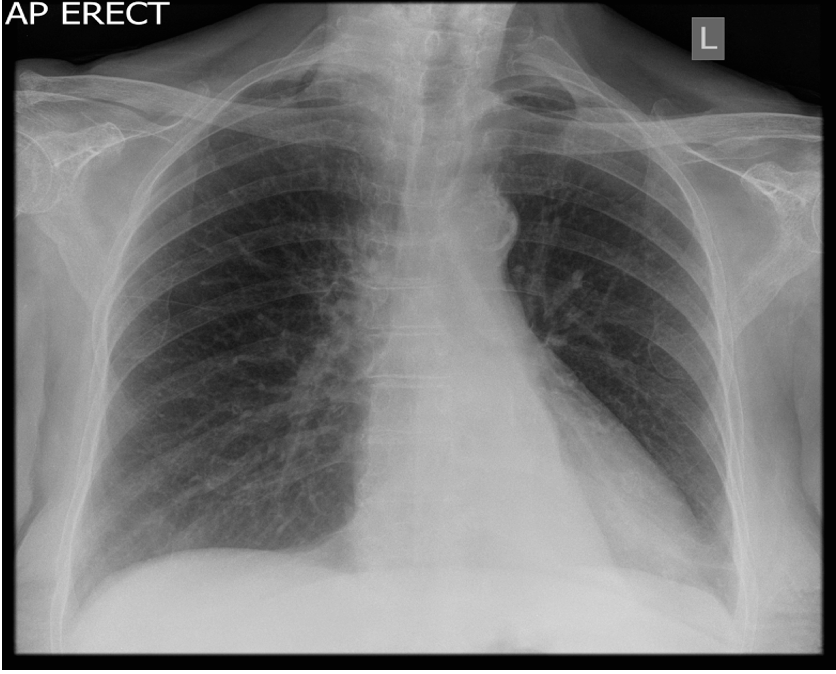

PA CXR

What is this showing? Collapse or consolidation?

Consolidation. Hilar are equal levels. Ill defined appearance